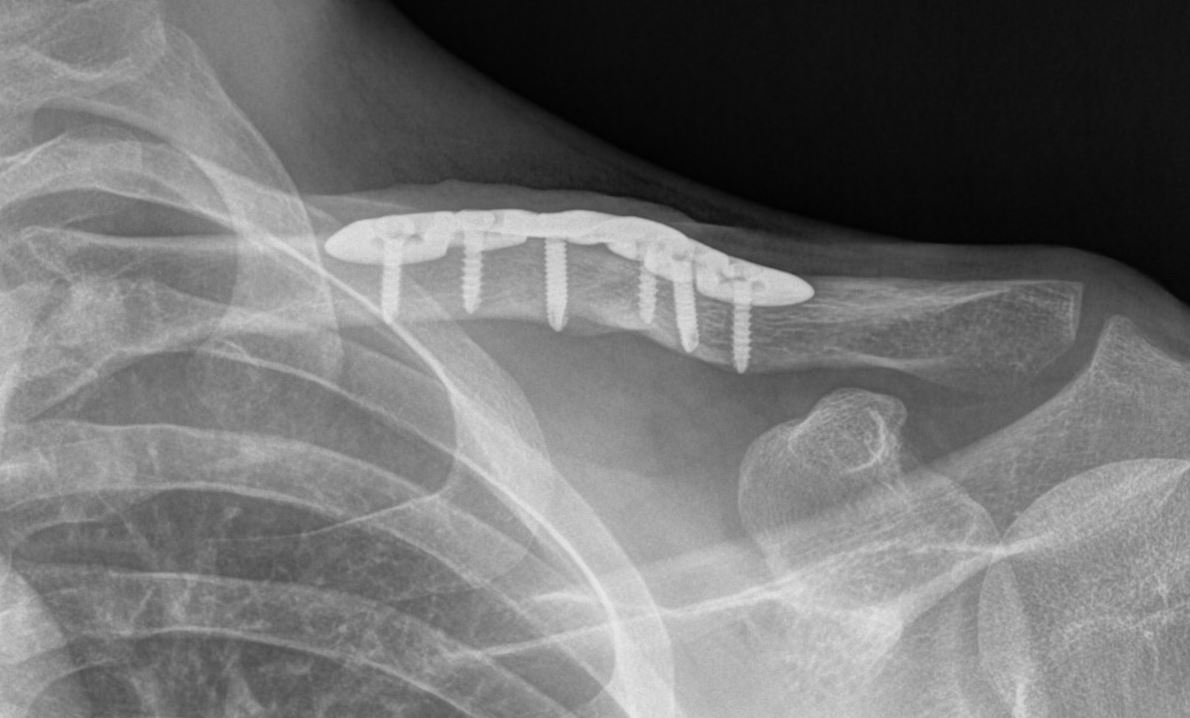

Eventuele operatie Slechts in bepaalde gevallen is er een reden voor een operatie. Een harde reden voor een operatie kan zijn dat een botstuk door de huid dreigt heen te gaan. Ook kan een sterk afwijkende stand een reden zijn voor een operatie. De nadelen van een operatie (ontsierend litteken, infectiekans, uitbreken van fixatiemateriaal) wegen echter vaak niet op tegen de voordelen (standscorrectie). Uw behandelend arts zal samen met u een afweging kunnen maken hoe dat in uw specifieke situatie is. Bij sleutelbeen breuken waarbij de breuk helemaal aan de zijkant ligt, zal er wel sneller naar een operatieve behandeling worden geneigd. Indien er voor een operatie wordt gekozen, zal er meestal gebruik worden gemaakt van een plaatje met schroeven.